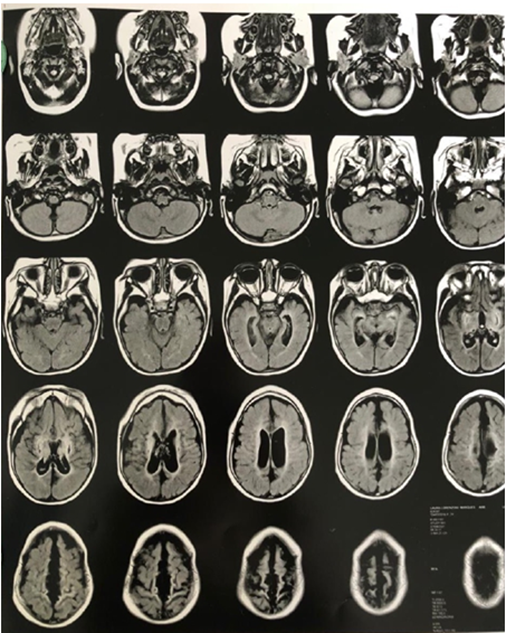

Neuroimaging: MRI (Figure-2) showed encephalomalacia and gliosis in the left parietal and occipital lobes with compensatory dilatation of the ipsilateral lateral ventricle. No cortical malformations or posterior fossa abnormalities.

Figure-2A: MRI showed encephalomalacia and gliosis in the left parietal and occipital lobes

Figure-2B: MRI showed encephalomalacia and gliosis in the left parietal and occipital lobes

Figure-2C: MRI showed encephalomalacia and gliosis in the left parietal and occipital lobes

Figure-2D: MRI showed encephalomalacia and gliosis in the left parietal and occipital lobes

Figure-2E: MRI showed encephalomalacia and gliosis in the left parietal and occipital lobes